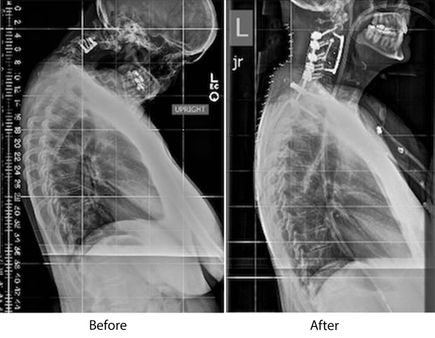

Before and after images show the drastic change in outlook for Vicki Hope, 56, of Boring, who underwent spinal repair surgery to correct a rare condition known as dropped head syndrome. (OHSU/Kristyna Wentz-Graff)

Her story began early in the year with what she initially believed to be a pinched nerve. Over the course of the year, she increasingly lost feeling in her fingers and legs as her head tilted forward. By the time she was referred to OHSU, her second vertebrae had slipped totally out of alignment, and her third and fourth vertebrae were degraded. The condition ultimately worsened to the point that her chin dropped to her chest – a rare condition known as dropped head syndrome.

First, however, Hope had to have her spine repaired in a complicated front-back operation. On Nov. 30, Khoi Than, M.D., an assistant professor of neurosurgery in the OHSU School of Medicine, removed Hope’s third and fourth vertebrae and replaced them with a cage packed with bone, a procedure known as anterior cervical corpectomy. She then had a posterior fusion spanning eight spinal levels. That followed two days of traction involving 40 pounds of weight attached to her head.